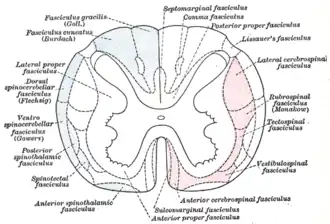

| Diagram of the principal fasciculi of the spinal cord. (In subacute combined degeneration of spinal cord, the "combined" refers to the fact that the dorsal columns and lateral corticospinal tracts are both affected, in contrast to tabes dorsalis which is selective for the dorsal columns.) | |

Subacute combined degeneration of spinal cord, also known as myelosis funiculus, or funicular myelosis,[1] also Lichtheim's disease,[2][3] and Putnam-Dana syndrome,[4] refers to degeneration of the posterior and lateral columns of the spinal cord as a result of vitamin B12 deficiency (most common), vitamin E deficiency,[5] and copper deficiency.[6] It is usually associated with pernicious anemia.

The onset is gradual and uniform. The pathological findings of subacute combined degeneration consist of patchy losses of myelin in the dorsal and lateral columns. Patients present with weakness of the legs, arms, and trunk, and tingling and numbness that progressively worsens. Vision changes and change of mental state may also be present. Bilateral spastic paresis may develop and pressure, vibration and touch sense are diminished. A positive Babinski sign may be seen.[7] Prolonged deficiency of vitamin B12 leads to irreversible nervous system damage. HIV-associated vacuolar myelopathy can present with a similar pattern of dorsal column and corticospinal tract demyelination.

Administration of nitrous oxide anesthesia can precipitate subacute combined degeneration in people with subclinical vitamin B12 deficiency, while chronic nitrous oxide exposure can cause it even in persons with normal B12 levels. Posterior column dysfunction decreases vibratory sensation and proprioception (joint sense). Lateral corticospinal tract dysfunction produces spasticity and dorsal spinocerebellar tract dysfunction causes ataxia.